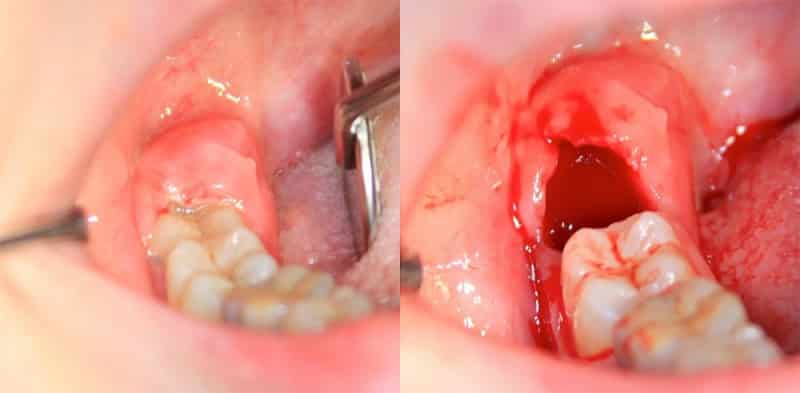

Удаление зуба может быть сопряжено с различными трудностями. Иногда коронка зуба полностью отсутствует, или же он разрушается в процессе удаления. В таких ситуациях стоматолог может прибегнуть к разрезанию десны, что, безусловно, приводит к более длительному процессу заживления.

После удаления зуба лунка заполняется кровью в течение нескольких минут (или до получаса, если использовались препараты для сужения сосудов), и образуется кровяной сгусток. Сгусток не следует извлекать из раны, так как он выполняет защитную функцию, препятствуя проникновению патогенных микроорганизмов. Удаление сгустка значительно увеличивает риск воспалительных процессов в деснах и мягких тканях ротовой полости.

Важно помнить, что при ослабленном иммунитете даже простое удаление зуба может значительно увеличить риск заражения лунки альвеолитом. Последствия этого можно увидеть на фотографиях гноя в лунке после удаления зуба.